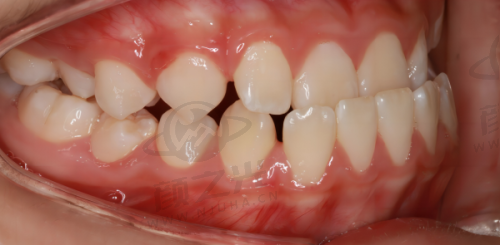

隐形矫正:提供隐形矫正服务,采用透明的矫正器,美观舒适且不易察觉。对于那些追求美观,不想因佩戴传统矫正器而影响形象的患者来说,是非常合适的选择。